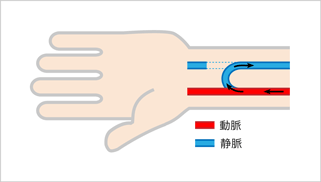

自己静脈内シャント

ご自身の動脈と静脈とを外科的に吻合して作製します。動脈から静脈に動脈圧の血液が流れこむことで、静脈が発達して太くなり、たくさんの血液が流れるようになります。高流量の血管が皮膚のすぐ下に出来ると、この血管を針で刺して血液透析で必要な血流量を、取り出し、そして返すことが可能となります。

初回作製では通常、利き手と反対側の手首近くで作りますが、静脈が細い場合や、2回目以降の作製では、前腕の中程肘近くで吻合したり、反対側上肢で作製したりすることになります。自己静脈内シャントは、他のバスキュラーアクセスと比較して、発達する、長期に開存している、感染に強いなどの長所があることから優先して作製されます。

自己静脈による内シャント手術は通常30~60分程度の手術時間で、局所麻酔下に行います。